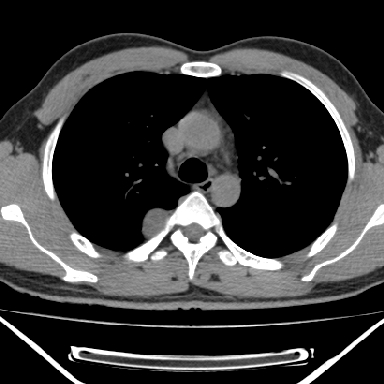

m 30 右胸痛10年

右上后纵隔脊柱旁类圆形肿块,边界光整,与胸腔呈钝角,首先考虑来源于肺外,神经源性肿瘤(神经鞘瘤可能大,神经鞘瘤)

m,30岁,右胸痛10年。

右上后纵隔旁软组织肿块影,与肺界面光滑,与胸壁呈钝角相交,提示肺外病变。位于肋骨下缘,边缘清楚,呈三角样指向与右侧椎间孔,但并示进入椎间孔;与对侧神经根对比,属同一走行方向。

考虑后纵膈良性肿瘤,神经源性肿瘤可能大。

鉴别:胸膜来源肿瘤。影像表现虽有肺外征象,但无胸水等相应佐证;再者,病史前10年,超长,与胸膜肿瘤不太吻合。

建议:再次查体,问清疼痛部位,如为1~2个肋间痛则神经源性肿瘤可能大,如疼痛较弥散,不按肋间分布,则可能为后纵膈其它来源肿瘤。

右上后纵隔脊柱旁类圆形肿块,边界光整,与胸腔呈钝角,首先考虑来源于纵膈,神经源性肿瘤可能大。

右上后纵隔脊柱旁见长椭圆形肿块,边界光整,与胸壁呈钝角。周围骨质未见异常。

考虑、1、后纵隔神经源性肿瘤;

2、不除外单发胸膜间皮瘤。